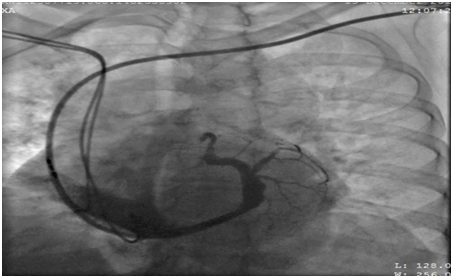

62 years old lady presented to the electrophysiology clinic with a history of shortness of breath, orthopnea, paroxysmal nocturnal dyspnea and lower limb swelling have started 3 weeks back. She denied any chest pain or syncope. She is known as HTN, IHD (S/P PCI to LAD 10 years ago), and History of Complete heart block (S/P DDDR pacemaker 6 years back). Previous LV function was normal (EF >55%, No significant valvular disease). On examination: She was conscious, oriented and vitally stable BP: 110/70 HR 70B/M, regular, RR: 22, Pso2: 96% on room air, T : 36.5, Congested neck vein observed, Chest: bilateral fine end in inspiratory basal crackles CVS: Normal S1, S2, no add sound or murmur Abdomen: Lax, soft, no masses Lower limb: Bilateral pitting edema ECG: well functioning paced rhythm; patient was diagnosed as new acute decompensate heart failure which was confirmed by ECHO showed: EF <35 %, with an impressive ventricular dyssynchrony, no significant valvular lesion, The patient was admitted in CCU as a case of ADHF (as a complication of RV pacing), was started on Ant failure treatment and the decision was taken to upgrade the DDDR TO CRTP. Then, Patient was driven in to Catha Lab. The procedure was initially attempted on the right, with successful cannulation of the right subclavian vein but unable to advance the guide wire to the superior vena cava (SVC), Venogram through the right anti-cubital vein showed a short occlusion of the right subclavian vein (Figure 1). The procedure was abandoned and LV lead implantation was performed on the left (Figure 2). Mild dissection of the coronary sinus occurred (Figure 3). Then sealed spontaneously and the LV lead was secured deeply in the posterolateral CS branch, a pair of long forceps were used for blunt dissection to create a subcutaneous tract from the right to the left. The proximal end of the LV lead was grasped with the forceps and tunneled above the sternum to rejoin the pocket (Figure 4). Then programming was done with good homeostasis.

- Fox et al. [14] describe the procedure using a pair of long forceps and blunt dissection to create a subcutaneous tract from the right to the left and

- Another technique is the placement of transvenous electrode from the contralateral side with subcutaneous, pre-sternal lead tunneling. Luthje et al described using regular chest tube and a trocar for this technique, and passing the lead in the chest tube to the other end. Thus, contralateral lead placement and subcutaneous pre-sternal TUN (like in our case) can be considered as a feasible option in a broad variety of patients. The optimal surgical approach, however, should be individualized for each subject.